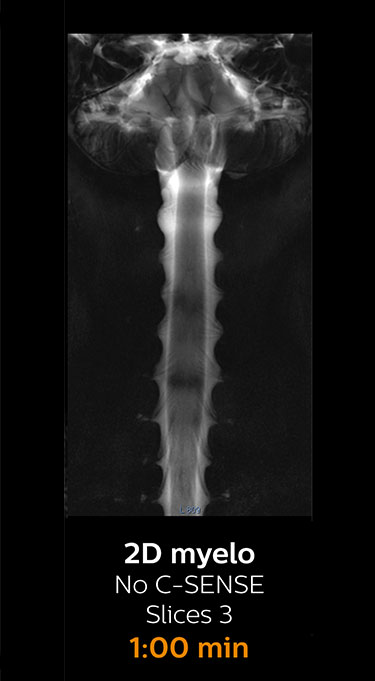

Fast MRI of cervical spine

With Compressed SENSE, the scan time for the routine cervical spine examination at KNC was reduced from 13:11 to 9:52 minutes, which corresponds to 25% reduction.

MRI examination of cervical spine with Compressed SENSE

MRI examination of the cervical spine with Compressed SENSE

Ingenia 3.0T CX

Scan time 9:52 min. (was 13:11 min. without Compressed SENSE)